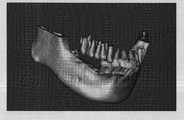

Figure 11 is the mandibular bone threedimensional model of rebuilding from the CT data.

Displayed map as a result behind Figure 29 registration: the relative position of (a) CT model and tartar cream model wherein; (b) relative position of implantation body and mucosa; (c) relative position of implantation body and upper tooth.